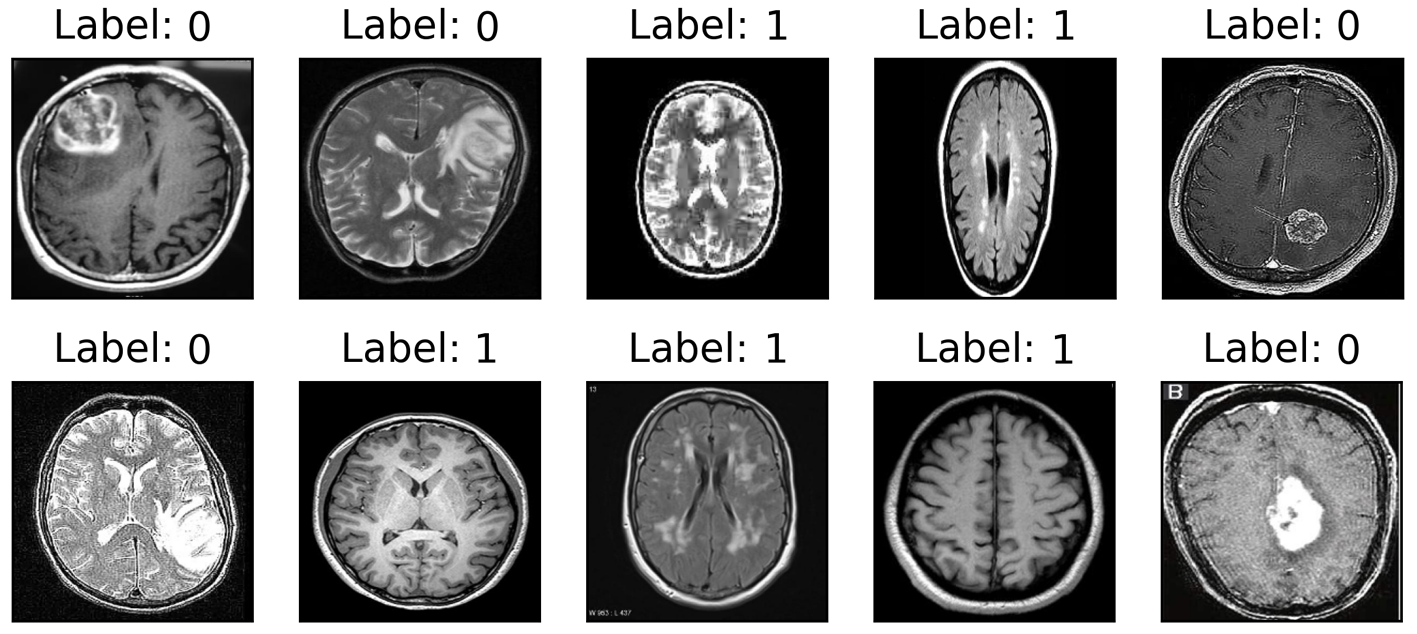

We evaluated the proposed method using four publicly available datasets to solve real-world BC tasks: malaria cells (MC) [19], brain tumors (BT) [20], solar cells (SC) [21], and crack surface (CS) [22] datasets (shown in Fig. 3). The MC dataset originated from the official National Institutes of Health (NIH) website containing cell images with equal instances of parasitized and uninfected cells from thin blood smear slide images of segmented cells. The BT dataset was obtained from a magnetic resonance imaging (MRI) technique consisting of samples with equal instances of a tumorous and healthy brain. The SC dataset contained sample images of functional () and defective () solar cells with varying degrees of degradation extracted from various solar modules. The CS contained color images with equal negative and positive crack samples collected from various Metu campus buildings. The image dimensionality of each dataset varies; thus, we resized them to pixels and normalized them in the interval . Each dataset was divided into 10-fold cross-validation to avoid bias. We split each dataset into an 80%:20% ratio for the training and testing sets, respectively; to obtain an optimal classifier, we employed a validation set that was subtracted by 20% from the training set.